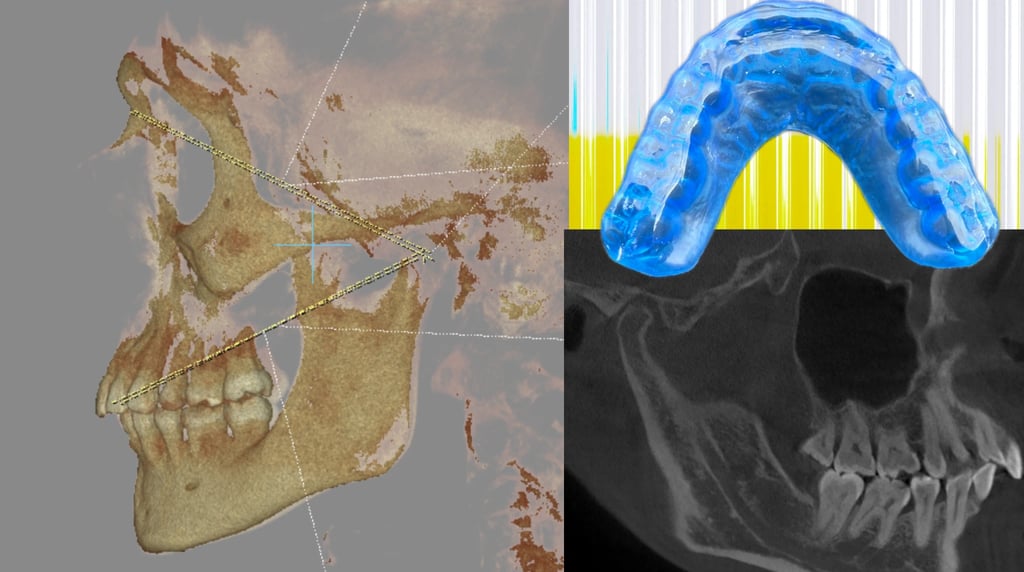

El uso de Tomografía Computarizada de Haz Cónico (CBCT) es indispensable en el protocolo moderno. A diferencia de una radiografía panorámica 2D, el CBCT nos ofrece una visión tridimensional de la relación cóndilo-fosa.

¿Qué buscamos? Signos de osteoartritis, aplanamiento condilar, reducción del espacio articular o desplazamientos discales evidentes.

El valor para el clínico: Esta "línea base" radiográfica nos permite saber si la articulación está saludable para soportar cambios oclusales o si estamos ante una patología degenerativa activa.

Gracias al flujo digital (CBCT + Escáner + Software de Planificación), en BILAB apoyamos la transferencia de esta posición mediante:

Planificación Virtual: Superponemos el CBCT con los escaneos intraorales para diseñar el tratamiento definitivo respetando la articulación.